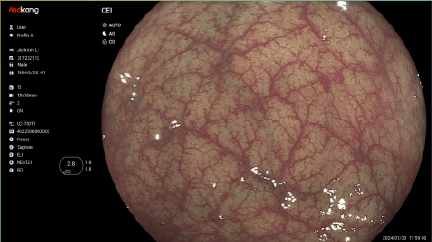

Dual Light Display Educational tool to shorten learning curve on optical chromoendoscopy image, by si- multaneously comparing white light image and chromoendoscopy image in real time